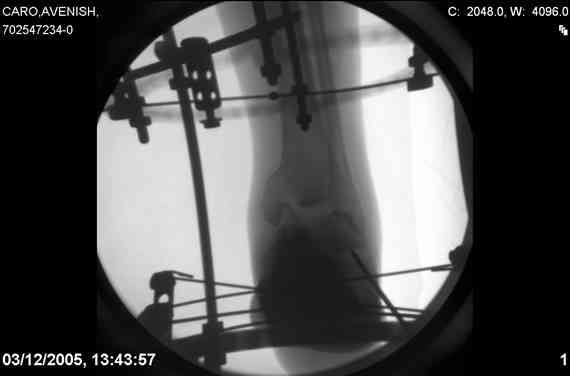

[Ortho] Осколчатый перелом таранной кости [1/2]

ya by popytalsya sobrat talus anatomichno,seichas pozdno operirovat

iz za oteka,po etomy distrakziya apparatom budet optmalna.Posyalu vam

podobyai moi sluchai.